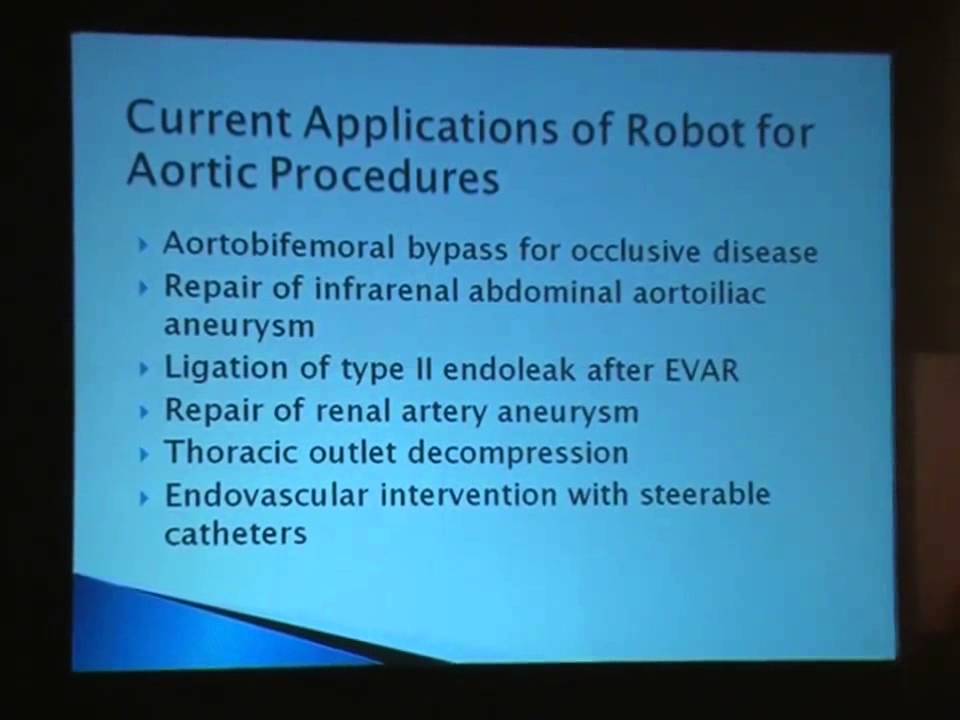

Vascular Robotic Surgery Overview